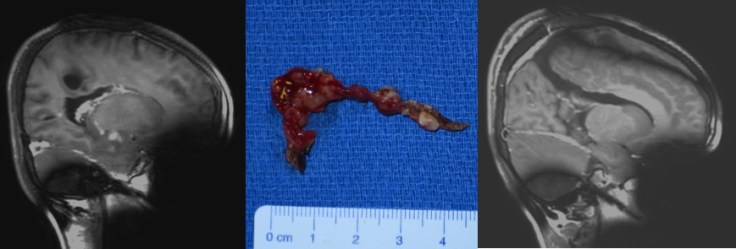

- de saignements répétés (cf. ci-contre)

l’abord des deux ventricules est possible par voie transcalleuse unilatérale ; c’est alors dans le ventricule contre-latéral qu’on est le plus à l’aise car l’axe de vision est parallèle au plan du ventricule. on ne peut cependant pas exciser la totalité des plexus car l’accès à la corne temporale est bloqué par la corona radiata.